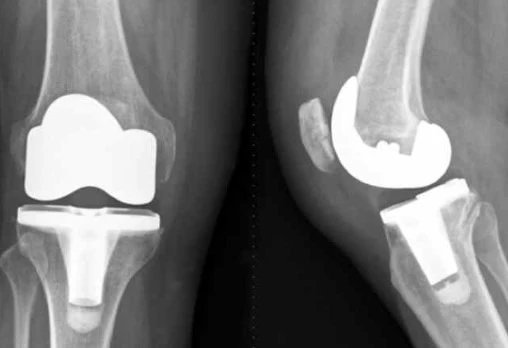

آرتروپلاستی دوطرفه زانو یکی از روش‌های مؤثر برای کاهش درد و بهبود عملکرد مفصل در بیماران مبتلا به آرتروز پیشرفته است. تقارن دقیق در قرارگیری پروتزها، طول اندام و تراز مفصل، نقش کلیدی در کاهش عوارض، افزایش دامنه حرکتی و بهبود کیفیت زندگی بیماران دارد. هرگونه عدم تقارن می‌تواند منجر به درد، ناپایداری و مشکلات مکانیکی شود. در این مقاله به بررسی اهمیت تقارن در آرتروپلاستی دوطرفه زانو، روش‌های جراحی، فاکتورهای کلیدی برای دستیابی به نتایج بهینه و مراقبت‌های پس از عمل پرداخته شده است.

تصویربرداری با اشعه ایکس و CT برای ارزیابی موقعیت پروتز و تقارن دو طرف.